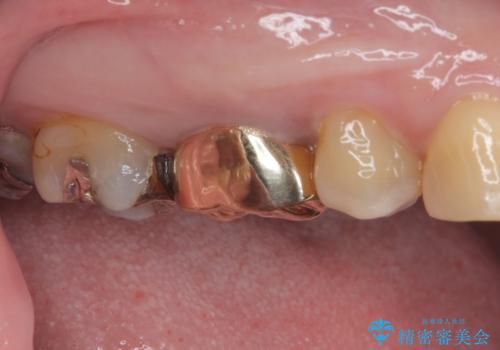

銀歯の下のむし歯 ゴールドクラウンによる補綴治療

- 奥歯で咬んだときに痛みがあり、物が挟まるとのことで来院された患者様です。

咬み合わせが非常に強く、見た目よりも機能と安定性を重視したいとのことで、PGAクラウン(白金加金合金クラウン)にて補綴する治療計画となりました。